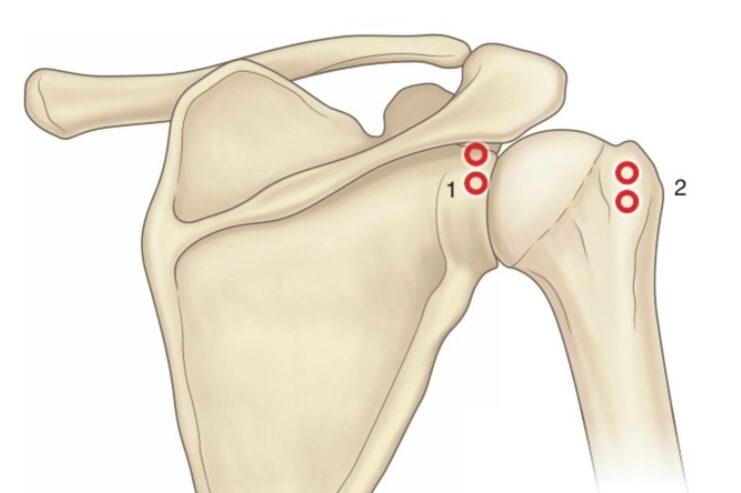

Common underlying causes are rotator cuff disorders, glenohumeraldisorders, acromioclavicular joint & frozen shoulder

What are the common conditions affecting shoulder joint?

Glenohumeral

1.Rotator cuff tendinopathy.

2.Rotator cuff tear

3.Subacromian bursitis

4.Glenohumeral arthritis

5.Glenohumeral instability

6.Labral tear

Extraglenohumeral

- Bicipital tendinopathy

- Acromioclavicular arthritis

- Subscapular bursitis